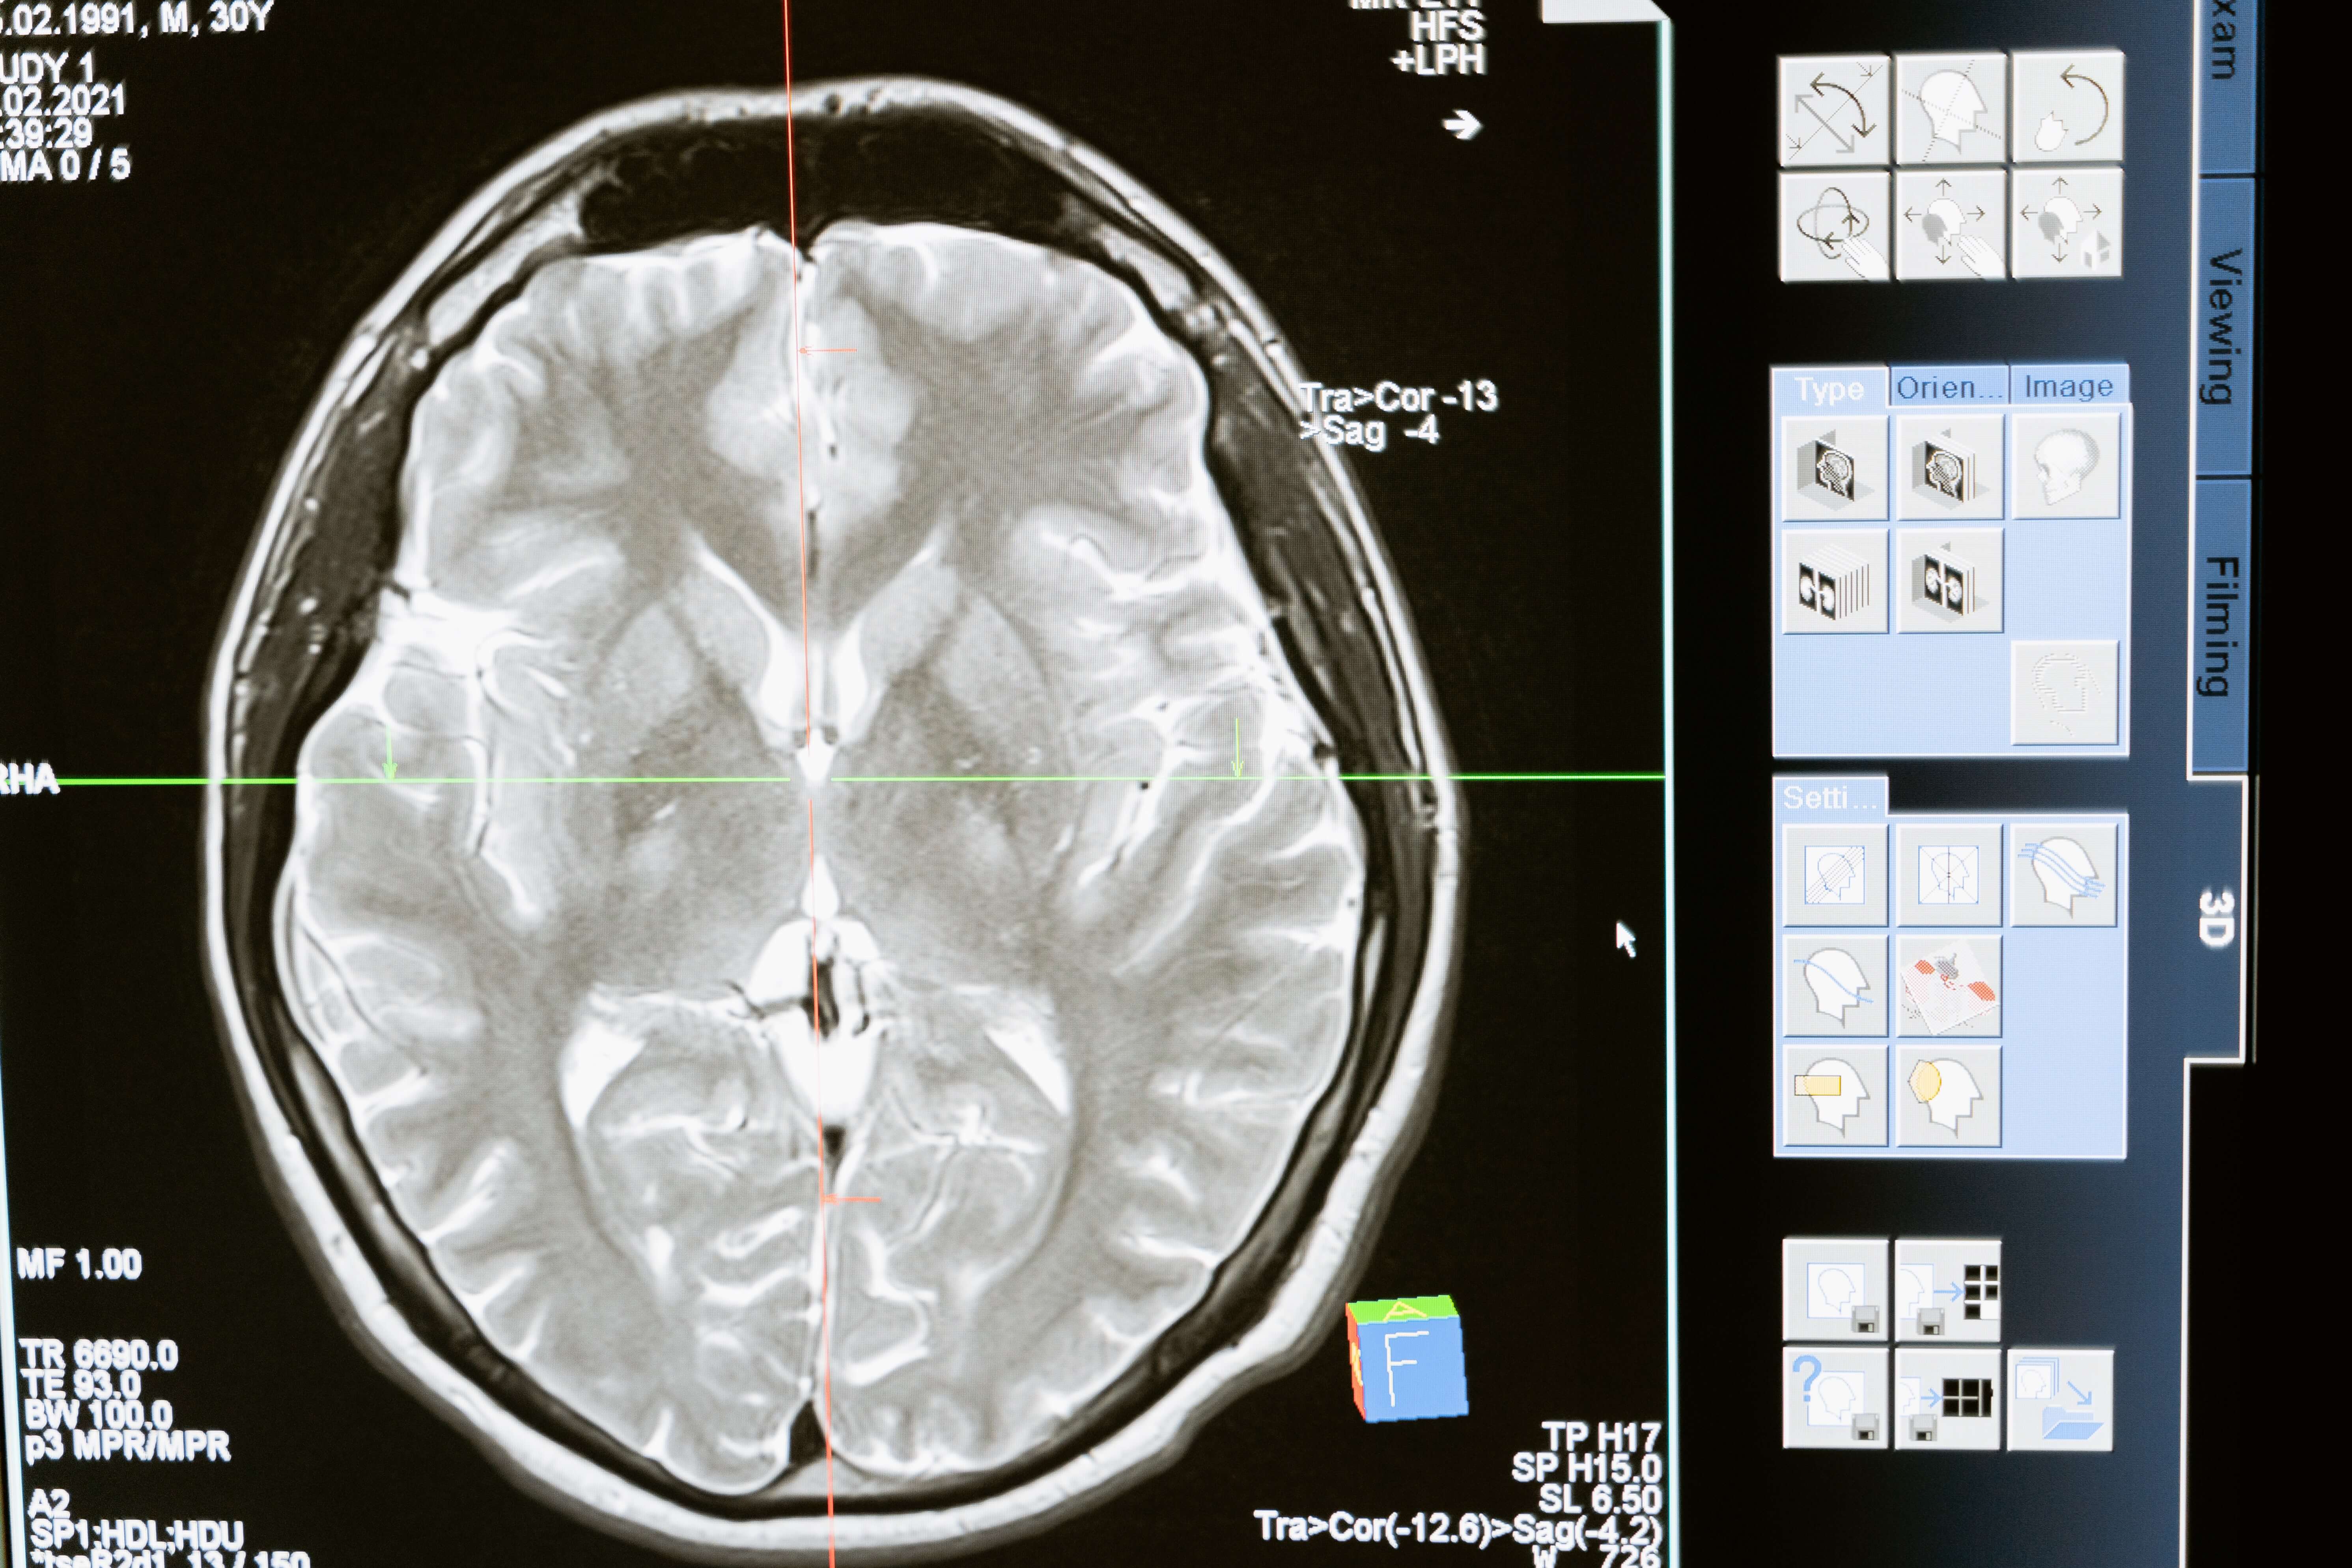

As residents know, scientists at the Lawrence Livermore National Laboratory have performed extensive research into the treatment of traumatic brain injuries, especially in blast-induced TBIs that occurred during the Iraq and Afghanistan conflicts. Here at home, TBIs continue to cause severe trauma, which can be life-changing. When a negligent driver or other entity is responsible for the trauma, the injured party may seek compensation with the assistance of the best Livermore brain injury lawyer.

What Are the Most Common Causes of a Traumatic Brain Injury?Traumatic brain injuries can be caused by jolts, bumps or even just the rapid back and forth movements of the head. While some TBIs may be minor and heal with time, others can have devastating results. There need not even be visible external injuries when trauma occurs to the brain. In some cases, not even noticeable symptoms are present at first but can increase with time. Others are readily apparent after the accident and require emergency medical care as well as long hospitalization. Causes of traumatic brain injuries are varied and the most common reasons include:

The severity of the injury varies depending on the type, and while minor injuries often don’t require hospitalization, more severe ones do. The extent of an injury and the complications that arise will determine the treatment and future prognosis for recovery. Following are the varieties of TBIs that can occur, most of which are caused by accidents:

- Concussions are considered the least serious of all TBIs. In a traffic accident or fall, you may suffer a concussion if jolted, bumped or receive a blow to the head. A rapid back and forth movement of the head often causes this kind of brain injury. In some people, headaches and cognitive changes may persist. Repeated concussions can lead to chronic traumatic encephalopathy (CTE), which causes memory loss, confusion and mood swings. It is most common in blast injuries, boxers and football players and is only diagnosed through autopsy.

- Hematomas are blood clots that usually form on the brain’s surface. There are many possible places where they can appear in the brain or between the skull and its protective covering, the dura mater. Hematomas may dissipate or worsen over time, necessitating surgical drainage or a craniotomy for treatment.

- An intracranial hemorrhage is bleeding between the skull and the brain itself. A buildup of blood and swelling can cut off oxygen to the brain, resulting in severe damage. A number of factors influence the prognosis and treatment, including location and severity.

- A fractured skull happens when the skull breaks or develops cracks. Injuries can sometimes be caused by pieces of the skull penetrating the brain. An infection or seizure can occur if cerebrospinal fluid leaks through the nose or ears due to a skull fracture.

- When the brain moves suddenly within the skull, the axons of the nerve cells can be severed, resulting in a diffuse axonal injury. When this happens, the brain is usually severely damaged. A severe enough trauma prevents nerve cells from communicating, resulting in permanent damage.